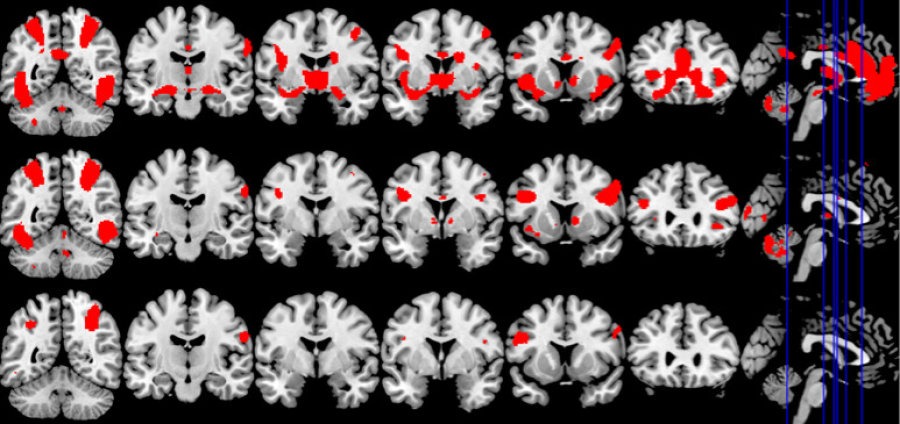

وقد عرض على المشاركين في الدراسة سلسلة من أشرطة الفيديو القصيرة التي تحتوي على محتوى جنسي صريح أو رياضة، في حين تم رصد نشاط الدماغ باستخدام التصوير بالرنين المغناطيسي الوظيفي (fMRI)، والذي يَستخدم إشارة تعتمد على مستوى الأوكسجين في الدم (BOLD) لقياس نشاط المخ.

وجد الباحثون أن ثلاث مناطق على وجه الخصوص كانت أكثر نشاطًا في أدمغة المرضى مع وجود سلوك جنسي قهري مقارنة مع المتطوعين الأصحاء، بشكل ملحوظ، كانت هذه المناطق هي كالآتي: (المخطط البطني “Ventral Striatum”، الأمامية الظهرية الحزامية “Dorsal Anterior Cingulate” واللوزة “Amygdala”)، وهي نفس المناطق النشطة بشكل خاص أيضًا لدى مدمني المخدرات عند ظهور المحفزات كالمخدرات، وتتشارك في منطقة المُخطط البطني (Ventral Striatum) أثناء معالجة المكافأة والدافع، في حين أن المنطقة الأمامية الظهرية الحزامية (Dorsal Anterior Cingulate) متورطة في توقع المكافآت وشغف المخدرات، وتشارك اللوزة (Amygdala) في معالجة الأحداث والانفعالات العاطفية المهمة.

وكما كان متوقعًا، أظهر المرضى الذين يعانون من سلوك جنسي قهري (Compulsive Sexual Behaviour) مستويات أعلى من الرغبة بعد مشاهدة أشرطة الفيديو الجنسية الصريحة، وارتبطت الرغبة أيضًا بارتفاع التفاعلات بين المناطق الدماغية المذكورة سابقًا ،لكن كان التفاعل بينها محدودًا بالمقارنة مع أشرطة الفيديو الرياضية الإيحائية.